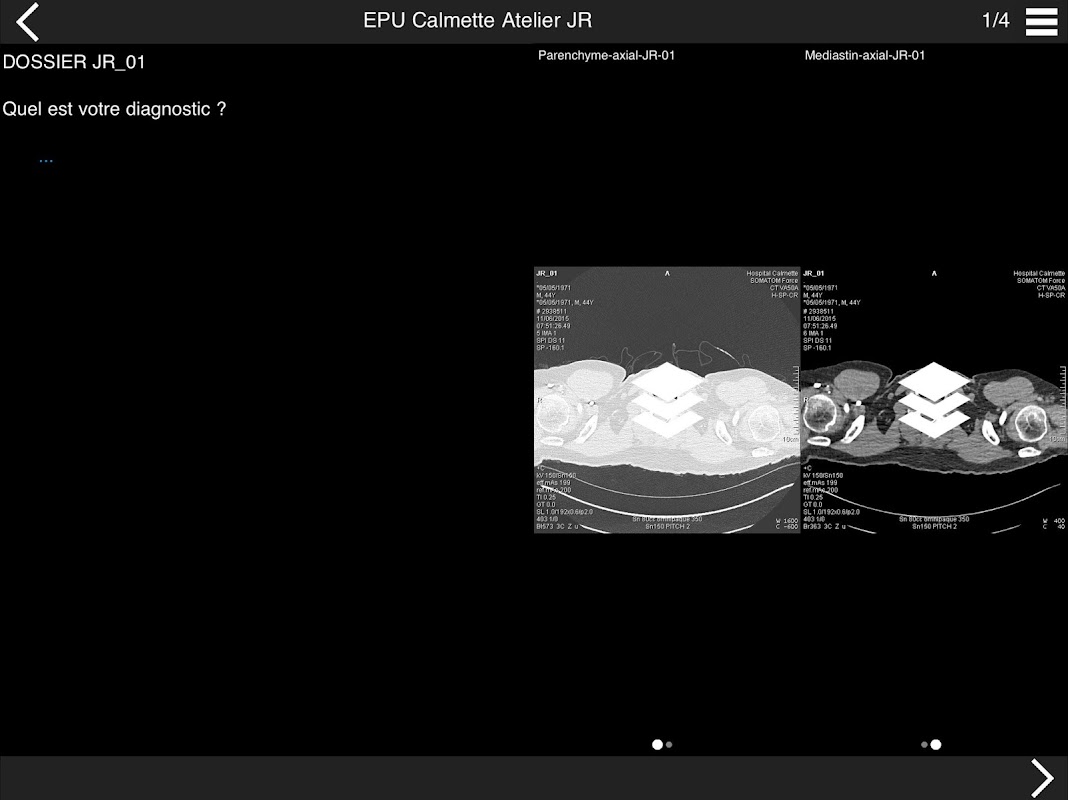

Retrouvez les cas cliniques du Cours intensif de TDM multicoupe du thorax dans cette application.